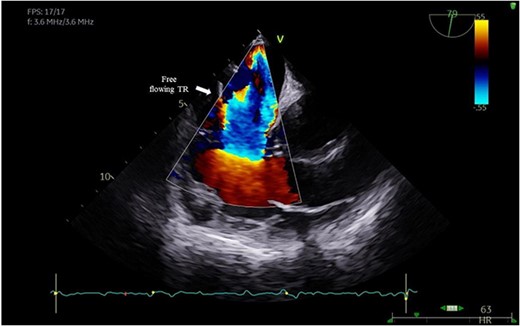

A 29-year-old man with a history of ventricular septal defect closure as a child, presented with severe multi-organ injuries after being run down by two cars. He was intubated on the scene by the hospital emergency medical services before being taken to the emergency department for haemodynamic stabilization and multiple imaging procedures. He suffered extensive bilateral degloving scalp lacerations and a haematoma due to bleeding from his left temporal artery. Computed tomography scan revealed bilateral multilevel rib fractures, a left-sided flail segment, bilateral haemopneumothoraces, and multifocal lung contusions, for which bilateral intercostal chest drains were inserted. Moreover, he had a shallow pneumopericardium, a subcapsular left renal haematoma, an extraperitoneal pelvic hematoma, displaced right-sided superior and inferior pubic ramus fractures as well as slight diastasis of the left sacroiliac joint. Although maximum resuscitation measures were taken with adequate fluid and blood product resuscitation, he remained persistently hypotensive and had worsening haemodynamics despite maximal inotropic support. A transoesophageal echocardiogram demonstrated a flail anterior leaflet of the TV and ruptured papillary muscle head (Fig. 1) with torrential tricuspid regurgitation (TR) and high right atrial (RA) pressures (Fig. 2).